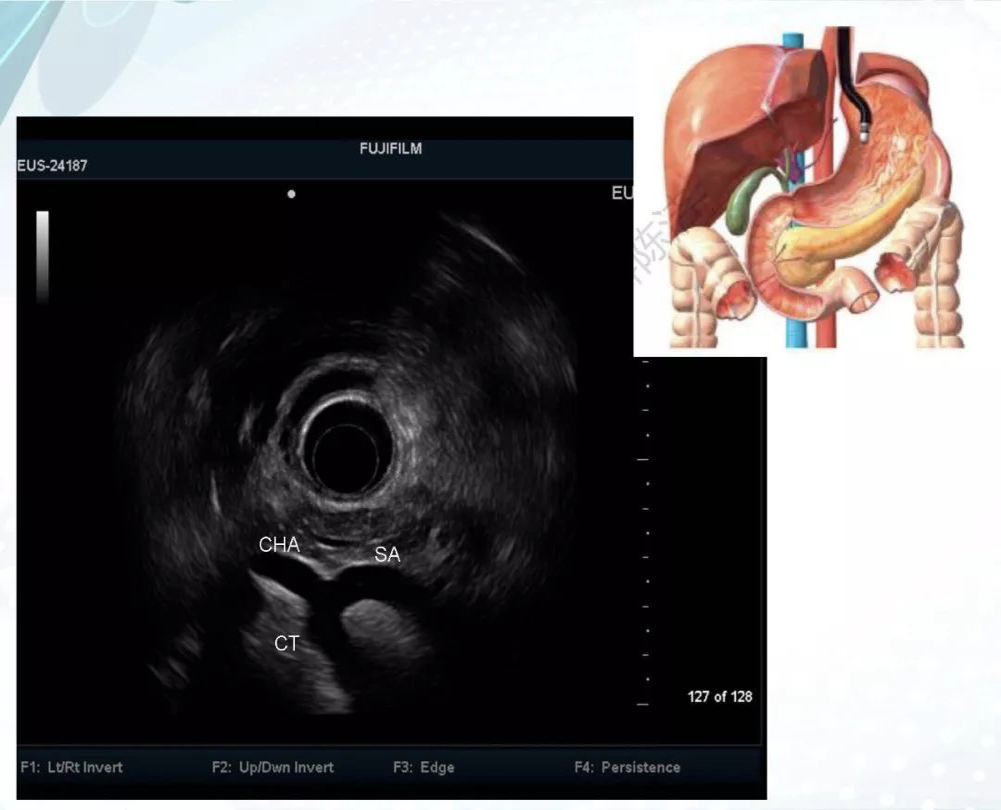

内镜超声检查术,英文名Endoscopic Ultrasound,简称EUS,是将内镜和超声相结合的消化道检查技术。该技术将微型高频超声探头置于内镜前端,当内镜插入体腔后,即可通过内镜直接观察管腔内的形态,又可同时进行实时超声扫描以获得管壁及周围邻近脏器的超声图像的技术。EUS将内镜对管腔粘膜的观察与超声的深部探测结合起来,为疾病提供了一种由表及里的诊断方法,极大的提高了内镜技术在临床上的应用价值。

随后,谭琰教授和蔡笃雄教授带领大家来到了我院消化内镜中心,由覃山羽教授亲自为患者检查并现场进行教学讲解,分析镜下病灶,制定治疗方案,并对来自海口市人民医院、琼海市人民医院、三亚中心医院等内镜医生分别进行手把手培训。现场学习氛围浓厚,学员们被精彩疑难的病例所深深吸引,深刻体会到超声内镜的魅力所在。